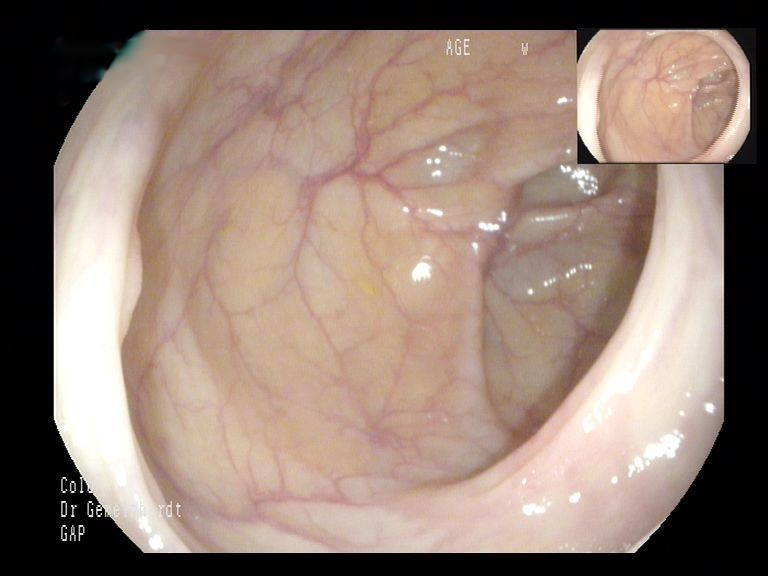

Im Rahmen der Koloskopie werden der gesamte Dickdarm sowie das Ende des Dünndarms (terminales Ileum) untersucht. Die Untersuchung wird in der Regel unter Sedierung durchgeführt, sodass der Patient keinerlei Schmerzen verspürt. Meist liegt die Untersuchungszeit bei unter 20 Minuten. Zum Einsatz kommen nur Geräte der neuesten Generation, die über höchste Bildqualität (HD, virtuelle Chromoendoskopie, künstliche Intelligenz) verfügen.

Darüber hinaus besteht die Möglichkeit, dass die Untersuchung mit Unterstützung durch künstliche Intelligenz (KI) durchgeführt wird. Die KI ersetzt dabei nicht den Untersucher, sondern unterstützt ihn, quasi wie eine "zweites digitales Augenpaar" bei der Suche nach Polypen. Während der Untersuchung wird das Live-Bild permanent mit einer riesigen, ständig wachsenden Datenbank verglichen und auf suspekte Befunde gescreent. Wird ein suspekter Befund entdeckt, wird der Untersucher optisch und akkustisch darauf hingewiesen und kann sich die Stelle gezielt ansehen und diese wenn nötig entfernen. Mehrere Studien konnten inzwischen zeigen, dass die Adenomdetektionsrate (ADR) als maßgebliches Maß der Untersuchungsqualität signifikant gesteigert werden kann, woraus eine höhere Untersuchungsqualität für Sie als Patient resultiert.